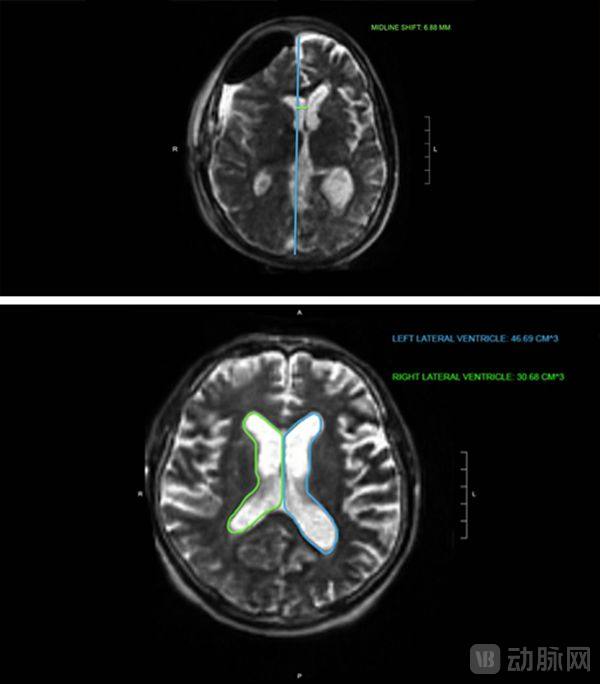

BrainInsight处理过程大约七分钟,包括中线移位(检测和测量)和侧心室(分割和体积测量)。

首先将Swoop系统获取的图像上传到云图像查看器,接着BrainInsight获取图像并进行自动计算,输出测量结果,并将图像进一步处理为颜色叠加层,其中每种颜色代表解剖结构的分割区域或空间测量值。

上:分析定位到中线最显著移位的切片。

中线(蓝线)、偏移(绿线)和中线偏移测量值

下:通过轴向扫描将左右侧脑室的轮廓及其计算体积可视化。

左(蓝线)和右(绿线)侧脑室周围的轮廓